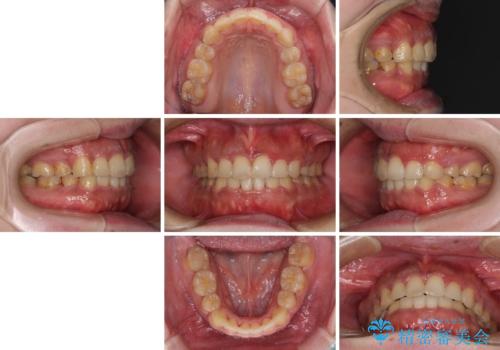

口元の突出感を改善 ワイヤー装置による抜歯矯正

- 口元の突出感と上下前歯のでこぼこを気にして来院された患者様です。

上下前歯部叢生のスペース獲得のため、上下顎左右小臼歯各1歯(計4本)を抜歯して、矯正治療を行うこととしました。

口腔内の清掃性に問題があり、虫歯のリスクが極めて高かったため、短期で治療を終えることを最優先に治療を進めました。